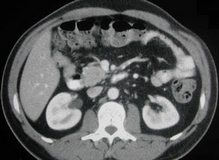

Pankreatik NET, tüm pankreas kanserlerinin yaklaşık yüzde 95’ini oluşturan pankreatik adenokarsinom’dan farklıdır.  Pankreatik NET nöroendokrin tümör denen ve vücuttaki hormon üreten hücrelerden kaynaklanan geniş bir grup kanserden biridir. ,  Pankreasta oluşan nöroendokrin tümörler, pankreatik NET olarak bilinirken, akciğer ve gastrointestinal yol da dahil, vücudun başka yerlerinde oluşanlar karsinoid tümörler olarak bilinir. Çoğu iyi diferensiye  pankreatik NET’ler tüm nöroendokrin tümörlerinin yaklaşık yüzde 22-28’ini oluştururlar. ,  Pankreatik NET hastalarının yaklaşık yüzde 90’ı ilk tanı anında lokal ileri veya metastatik hastalık tanısı alırlar.  Metastazı olan pankreatik NET hastalarının prognozu zayıf, sağkalımları ise metastatik meme kanseri veya metastatik kolon kanserine benzer şekilde, ,  yalnızca 1-3 yıldır.

SUTENT kanserin büyümesi, çoğalması ve yayılmasında rol oynadığı belirlenen çoklu moleküler hedefleri bloke ederek etki eden, oral multi-kinaz inhibitörüdür. SUTENT’in iki önemli hedefi plan vasküler endoteliyel büyüme faktörü reseptörü (VEGFR) ve platelet-kökenli büyüme faktörü reseptörü (PDGFR), pek çok solid tümör tipi tarafından salgılanmakta ve tümörlerin kan damarı oluşumu yoluyla büyümeleri için gereken oksijen ve besinleri aldıkları anjiyogenez sürecinde kilit rol oynadıkları düşünülmektedir. SUTENT ayrıca tümör büyümesi için önem taşıyan, KIT, FLT3 ve RET gibi başka hedefleri de baskılamaktadır.